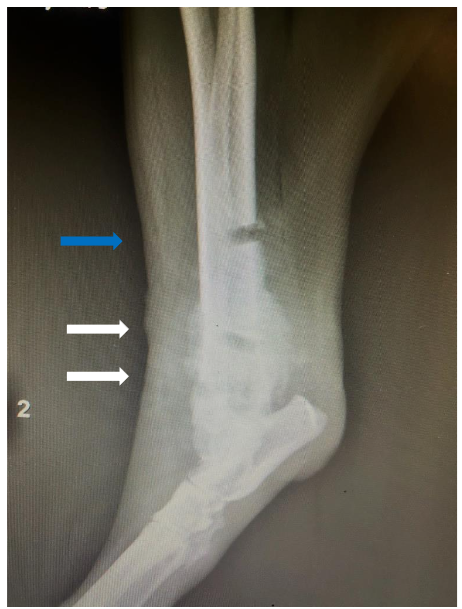

7-year-old, spayed female, Bull Mastiff with a distal tibial bony lesion (Fig. 3). She had an intermittent toe touching lameness of the right hindlimb. Initially, bone biopsies with histopathology were performed to only arrive at reactive bone (Fig. 3, blue arrow). This case drives home that if the tissue sampled does not encompass the root cause or nidus, the definitive diagnosis may be missed.

Caveats

Case 2 (Fig. 3) demonstrates the difficulties of getting a diagnostic sample. Employing multiple diagnostic tools were useful to overcome this limitation. Fine-needle aspiration biopsy requires quick execution for diagnostic material to be obtained. The interpretation of neoplasia may be diminished when cells are diluted in extraction from tissue easily derived in spreading them onto a glass slide. The nuclei can easily fall or collapse into the background, leading to an inaccurate diagnosis.

7-year-old, spayed female, Bull Mastiff, plain lateral radiograph of the right femur where a bony reactive lesion (white arrows). Subsequent to this, fine-needle aspirate biopsy was performed and cytology was performed to confirm a diagnosis of osteosarcoma.